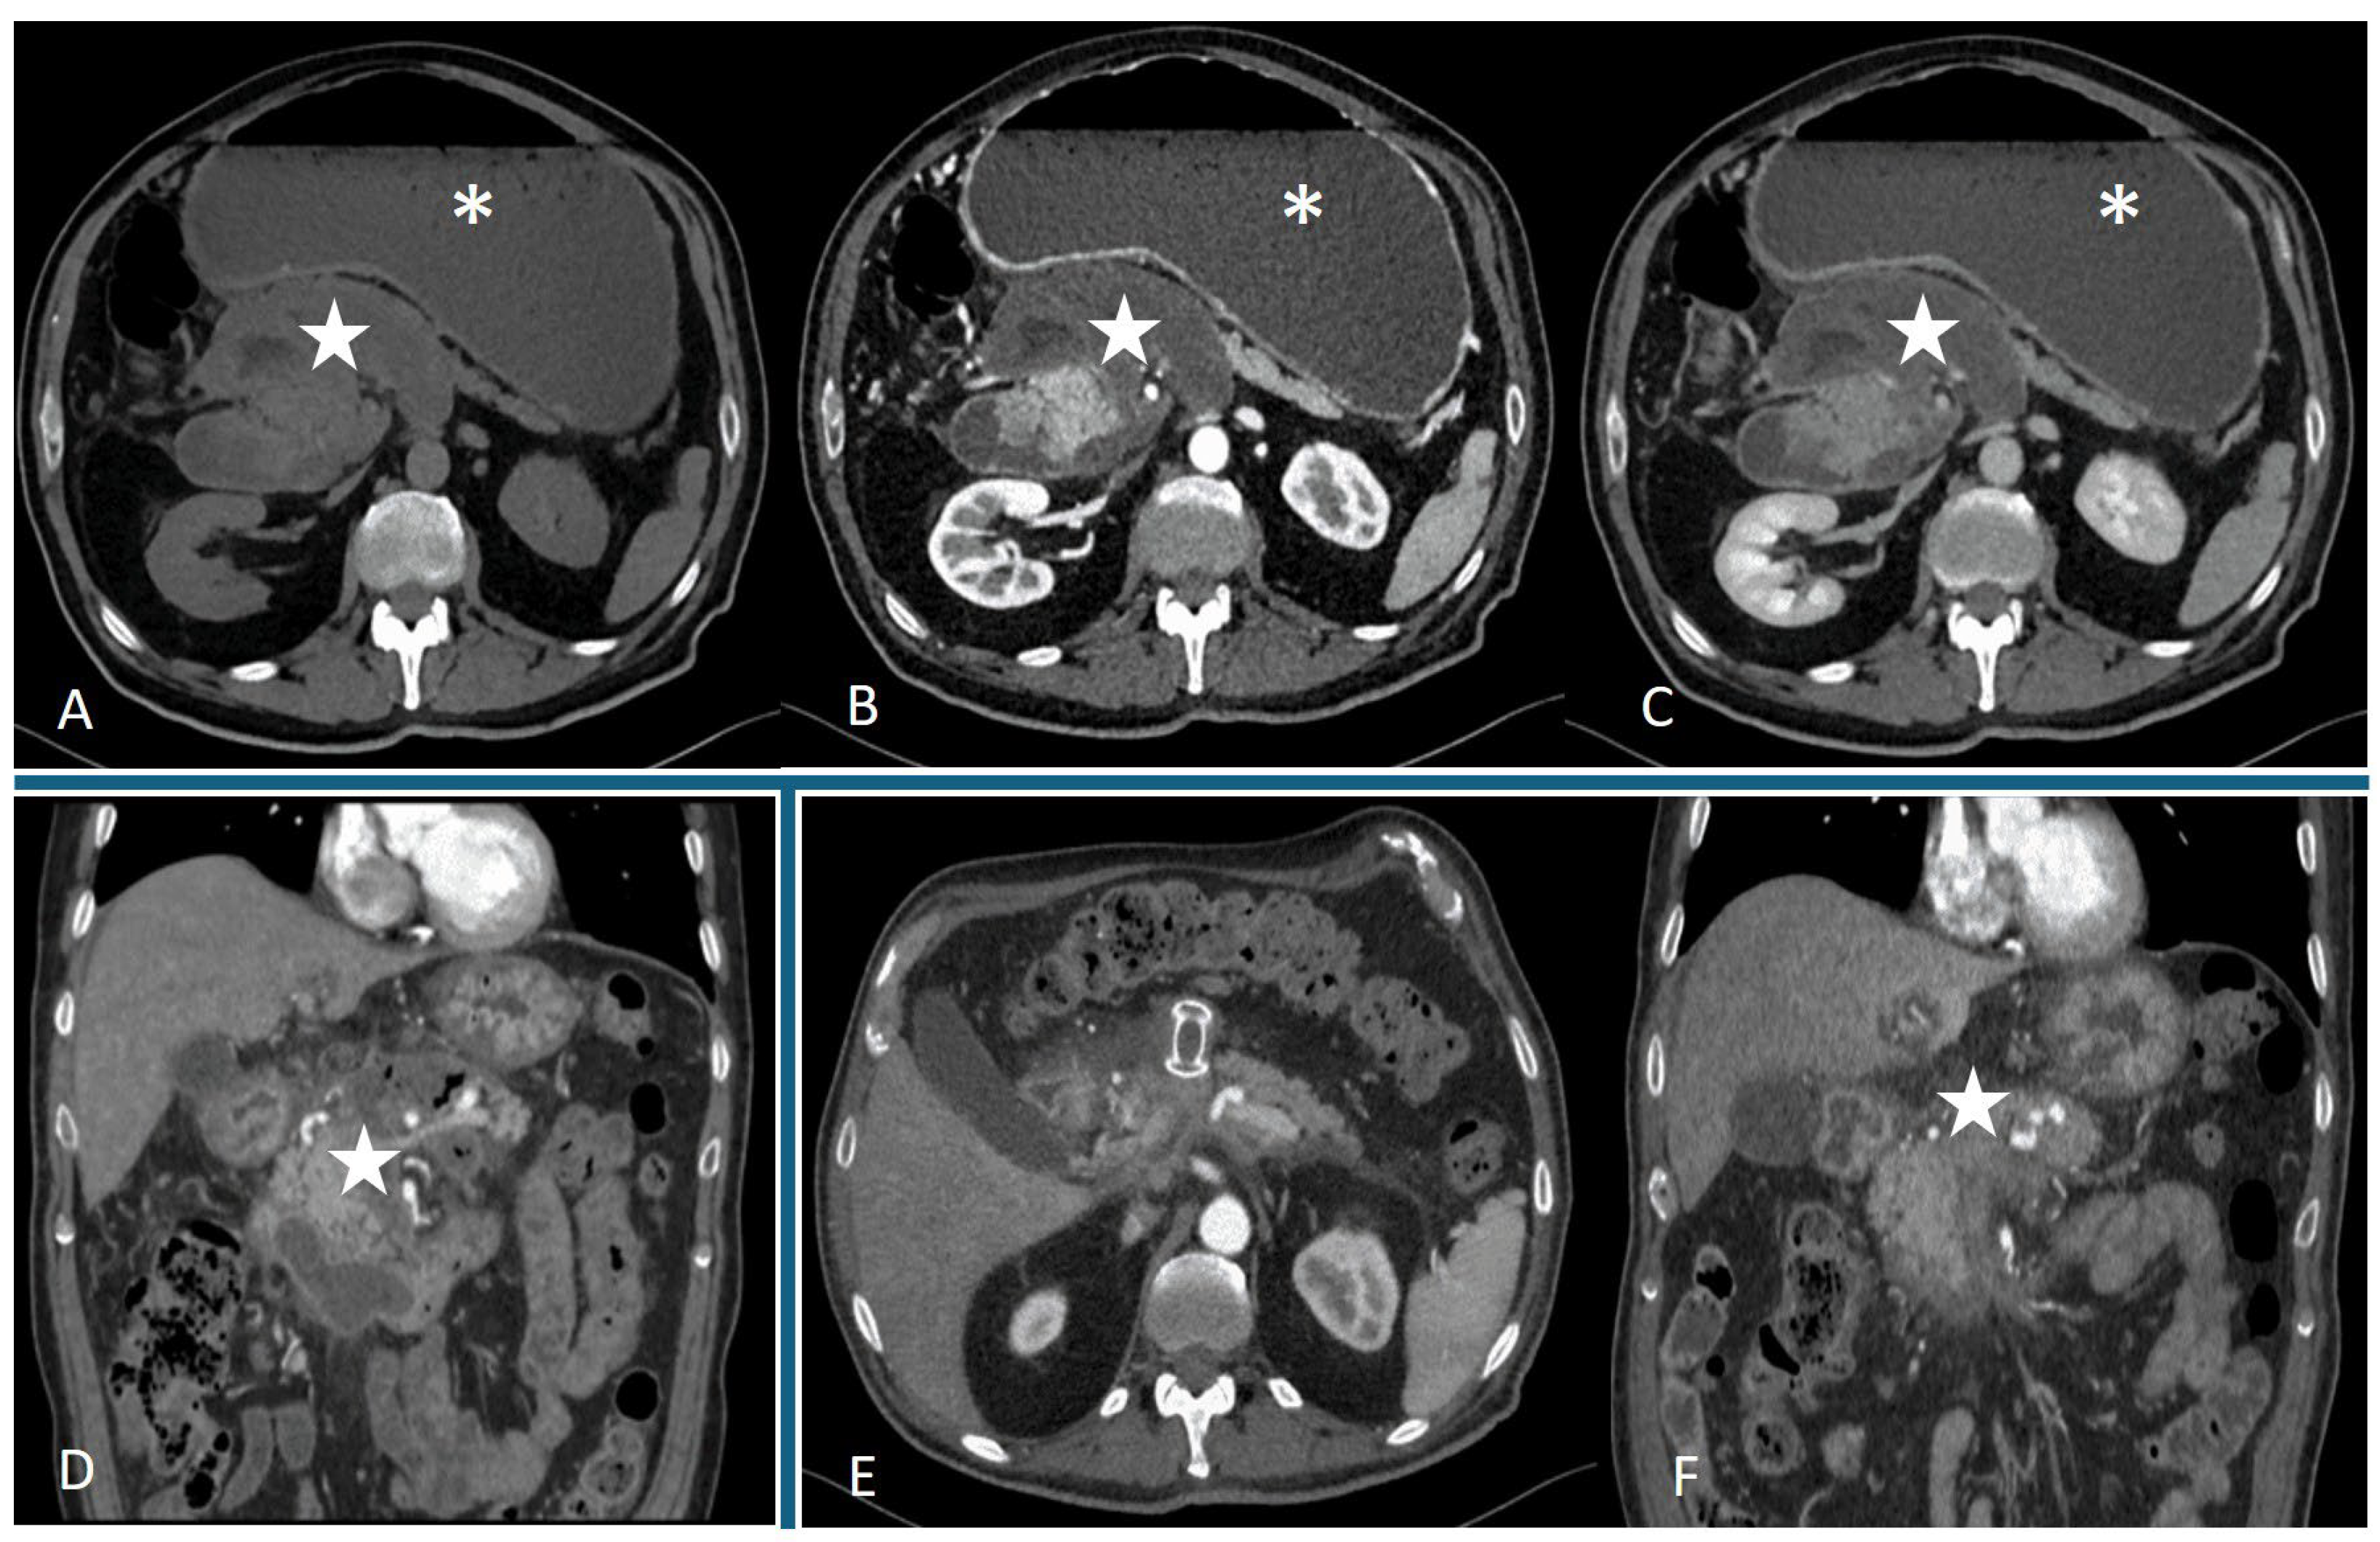

4.1. Role of Computed Tomography (CT)

- Dhaka, N.; Samanta, J.; Kochhar, S.; Kalra, N.; Appasani, S.; Manrai, M.; Kochhar, R. Pancreatic fluid collections: What is the ideal imaging technique? World J. Gastroenterol. 2015, 21, 13403–13410. [Google Scholar] [CrossRef] [PubMed]

- Foster, B.R.; Jensen, K.K.; Bakis, G.; Shaaban, A.M.; Coakley, F.V. Revised Atlanta Classification for Acute Pancreatitis: A Pictorial Essay. Radiographics 2016, 36, 675–687. [Google Scholar] [CrossRef]

- Thoeni, R.F. The revised Atlanta classification of acute pancreatitis: Its importance for the radiologist and its effect on treatment. Radiology 2012, 262, 751–764. [Google Scholar] [CrossRef]

- Takahashi, N.; Papachristou, G.I.; Schmit, G.D.; Chahal, P.; LeRoy, A.J.; Sarr, M.G.; Vege, S.S.; Mandrekar, J.N.; Baron, T.H. CT findings of walled-off pancreatic necrosis (WOPN): Differentiation from pseudocyst and prediction of outcome after endoscopic therapy. Eur. Radiol. 2008, 18, 2522–2529. [Google Scholar] [CrossRef]